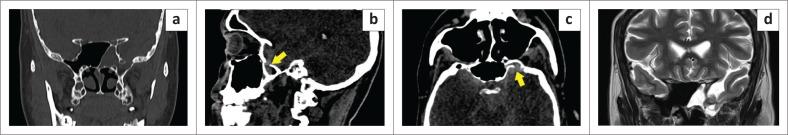

Intrasphenoidal encephalocoeles are acquired or congenital herniations of meninges and brain parenchyma through a structural sphenoid bone defect. Acquired causes are most common, either iatrogenic, post-traumatic, or spontaneous. However, defects in the lateral wall of the sphenoid sinus are uncommon and cephalocoeles through them relatively underexplored in current literature, warranting dedicated attention to unravel their complexities. Congenital causes such as persistence of Sternberg's canal, which can lead to lateral cephalocoeles, is a rare entity, seen in two of the presented cases, based on the location of the defect with respect to the line connecting the foramen rotundum and the vidian canal (VR line). Three cases of intrasphenoidal cephalocoeles are presented; two patients presented with watery nasal discharge without prior trauma or surgery and the third case was incidentally detected in an elderly patient with intraparenchymal haemorrhage. Imaging with CT cisternography and brain MR were performed to ascertain the exact location of the leak and confirm the presence of herniated brain tissue via the defects. Patients were evaluated by otolaryngology for transnasal endoscopic repair, which was deemed unfeasible, and referred to neurosurgery for transcranial duroplasty.

蝶窦内脑膨出是指脑膜和脑实质通过蝶骨结构缺损形成的后天性或先天性疝出。后天性病因最为常见,包括医源性、创伤后或自发性病因。然而,蝶窦外侧壁缺损并不常见,目前文献中对通过这些缺损形成的脑膨出研究相对较少,因此需要专门关注以揭示其复杂性。先天性病因如施特恩贝格管持续存在可导致外侧脑膨出,这是一种罕见情况,在所呈现的两例病例中可见,其依据缺损相对于连接圆孔和翼管的线(VR线)的位置而定。本文呈现了三例蝶窦内脑膨出病例;两例患者表现为水样鼻溢液,无既往创伤或手术史,第三例在一名老年脑实质内出血患者中偶然发现。进行了CT脑池造影和脑部磁共振成像以确定漏口的确切位置,并通过缺损确认疝出脑组织的存在。患者接受了耳鼻喉科评估以进行经鼻内镜修复,但认为不可行,随后转诊至神经外科进行经颅硬脑膜成形术。